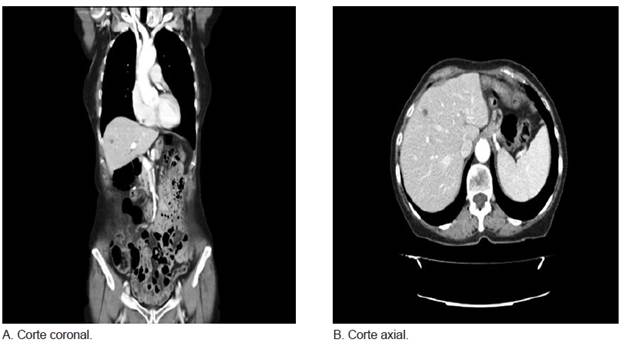

Paciente de sexo femenino, de 75 años de edad, con antecedentes personales de hipertensión arterial, colecistectomía y gastrectomía total con esofagectomía distal por tumor neuroendocrino. En seguimiento por el servicio de Oncología, clínicamente asintomática y con examen físico normal. Se realizó una tomo-grafía computarizada (TC) abdomino-pélvica de control a los dos años, en la que se objetivó una lesión de ocupación hepática en segmento IVb, hipervascularizada, de 7 mm, sugerente de metástasis (figura 1). Se complementó el estudio con una resonancia magnética (RM) de hígado, la cual mostró aumento de señal en T2 que insinuaba el mismo diagnóstico. Los estudios analíticos complementarios estaban dentro de los parámetros normales. Se decidió realizar una intervención quirúrgica programada con intención curativa.